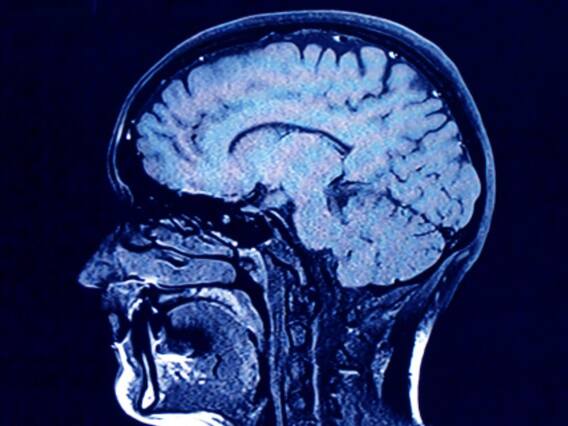

How Cognitive Function Is Influenced By Lifestyle Choices?

The Mind-Body Connection: Fuel For The Brain

Smita Das Jain who is a Personal Empowerment Life Coach said, "Consider the mind-body connection as fuel for the brain. The primary constituents are regular exercise, a nutritious diet, and sufficient sleep. Engaging in regular physical activity oxygenates the brain, enhancing cognitive abilities. A well-balanced diet comprising fruits, vegetables and brain-boosting nutrients nurtures and reinforces mental clarity. Quality sleep, on the other hand, supports memory consolidation and cognitive sharpness."